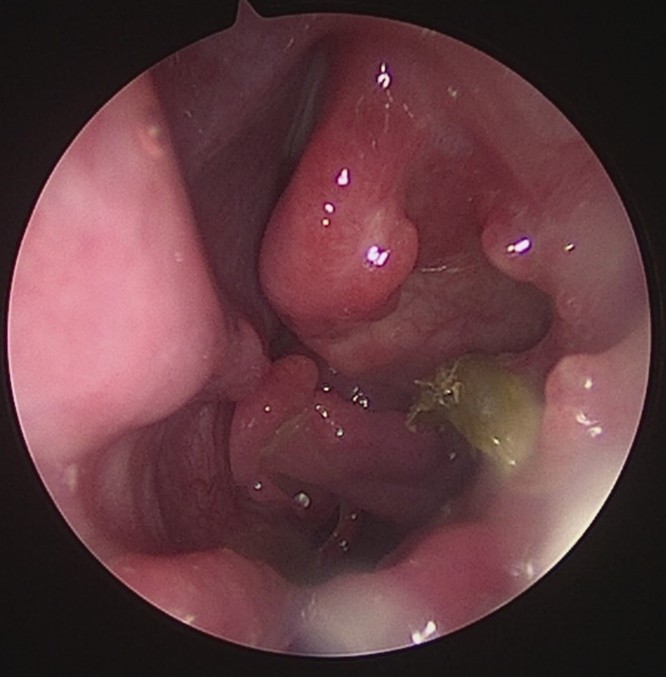

- Zunge 8 Wochen nach dem Eingriff – Es konnte eine Reduktion der Dicke von fast 1 cm erreicht werden.

Die Volumenreduktion des Zungengrundes wird bei Patienten eingesetzt, die eine Vergrößerung oder Erschlaffung der Zungenmuskulatur aufweisen. Der Zungengrund wird durch den Eingriff stabilisiert und die Atemwege erweitert. Die Gewebe- und Organoberflächen bleiben intakt, was kaum zu postoperativen Schmerzen führt, und das Infektionsrisiko vermindert. Eine sichtbare Volumenreduktion und Straffung des Gewebes ist innerhalb von 6 Wochen zu sehen. Meist sind nur zwei Behandlungstermine notwendig.

Hierbei kommt die CELON Methode zum Einsatz- Es handelt es sich um eine bipolare radiofrequenzinduzierte Thermotherapie (RFITT) die eine minimalinvasive und impedanzkontrollierte Gewebeablation darstellt. Diese Methode ist sehr schonend, schnell und hoch effizient. Der Patient kann nach der Behandlung die Praxis sofort verlassen und hat somit keine Ausfallszeiten. Diese Methode schützt die Organoberflächen (Mukosa, Flimmerepithel) und verursacht keine Schmerzen während und nach dem Eingriff.